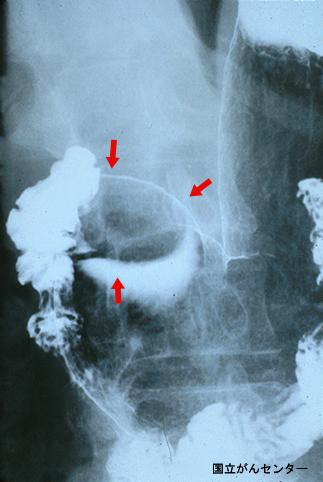

Típico Lipoma Gástrico

[Image-ID:4431]

Tumor no Epitelial Benigno/Lipoma

parte(separada por órganos)

estómago(región)/antro

método de exámen

Rayos X

diámetro mayor del tumor